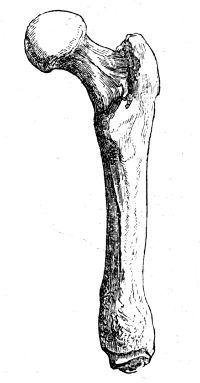

| Alterations of Form in the Head of the Femur | 86 |